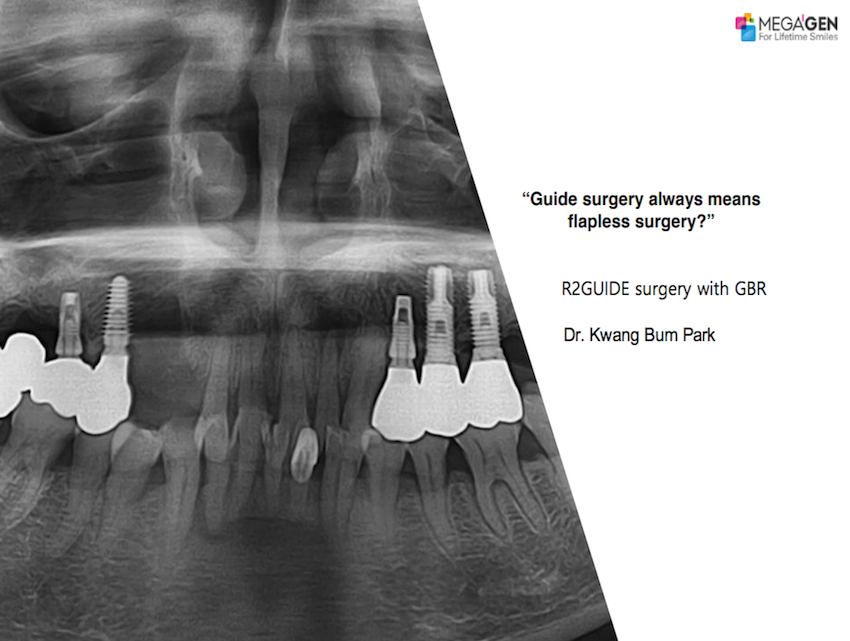

Dr. Michiko Noguchi,Aesthetic Zone,Immediate loading,Maxillary Anterior,#11,#13,#21,Root Membrane,AnyRidge,MEGA ISQ,Root Membrane Kit,Poster